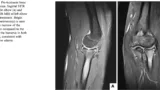

16時に病棟に上がって, 大学病院から転院してこられた患者さんの紹介状やこれまでのX線写真などの資料を確認しました. 高所から墜落して両手を地面に着いたために, 両方の肘関節が脱臼して骨折された患者さんでした. 両方の肘関節を同時に脱臼した患者さんを診るのは, 初めてでした.

この患者さんは, すでに大学病院で骨折と靱帯を修復する手術が行われており, 当院にはリハビリテーションを目的として転院されました.

手術は1カ月ほど前でしたが, 手術時にヒンジ式創外固定(皮膚の外側から骨にネジが刻まれた金属製の棒(ピン)を差し込んで, このピンを体外で器械で固定して患部の安静を保つ一方, 肘関節の曲げ伸ばし運動は可能とする治療)を併用されて, 手術後早い時期から肘関節を動かすようにしていたそうです. 先週, 創外固定は外されて, その後当科に転入院されました. 肘関節を動かしてもらうと, 予想外に肘関節の動きがよくて, 両手とも顔までとどくくらいに肘関節が曲がるので, 大変驚きました.